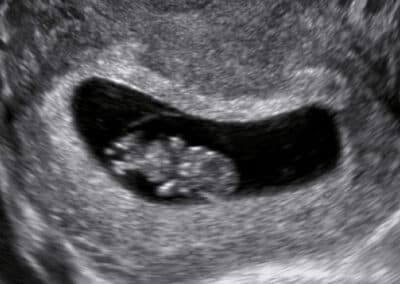

Vyšetření budoucího miminka v 6.týdnu těhotenství

Ultrazvukové vyšetření v časném (6. – 10. týdnu) těhotenství Hlavním cílem ultrazvukového vyšetření v časném těhotenství, respektive v 6.-10. týdnu těhotenství, je potvrdit normálně se vyvíjejícího těhotenství v děloze a určit jeho četnost. Do 8. týdne se vyšetření obvykle provádí při prázdném močovém měchýři přes pochvu (vaginální ultrazvuk) a od 9. týdne těhotenství při plném močovém měchýři přes břišní stěnu.

V časném těhotenství vám v našem centru vyšetříme:

umístění těhotenství v děloze, případně mimo dělohu počet miminek (jednočetné těhotenství, dvojčata, trojčata či vícerčata) srdeční akci miminka stanovíme stáří miminka a termín předpokládaného porodu od 8. týdne již zkontrolujeme základy končetin a vývoj mozku miminka